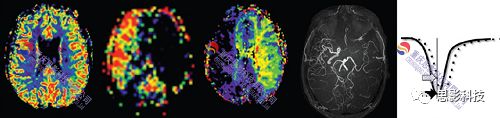

3. ASL腦網(wǎng)絡分析

1) 對多時間點的ASL數(shù)據(jù),計算腦血流值,并依據(jù)模板計算腦區(qū)間的相關,構建腦網(wǎng)絡。

2) 腦網(wǎng)絡指標(如節(jié)點效率等)計算、統(tǒng)計。